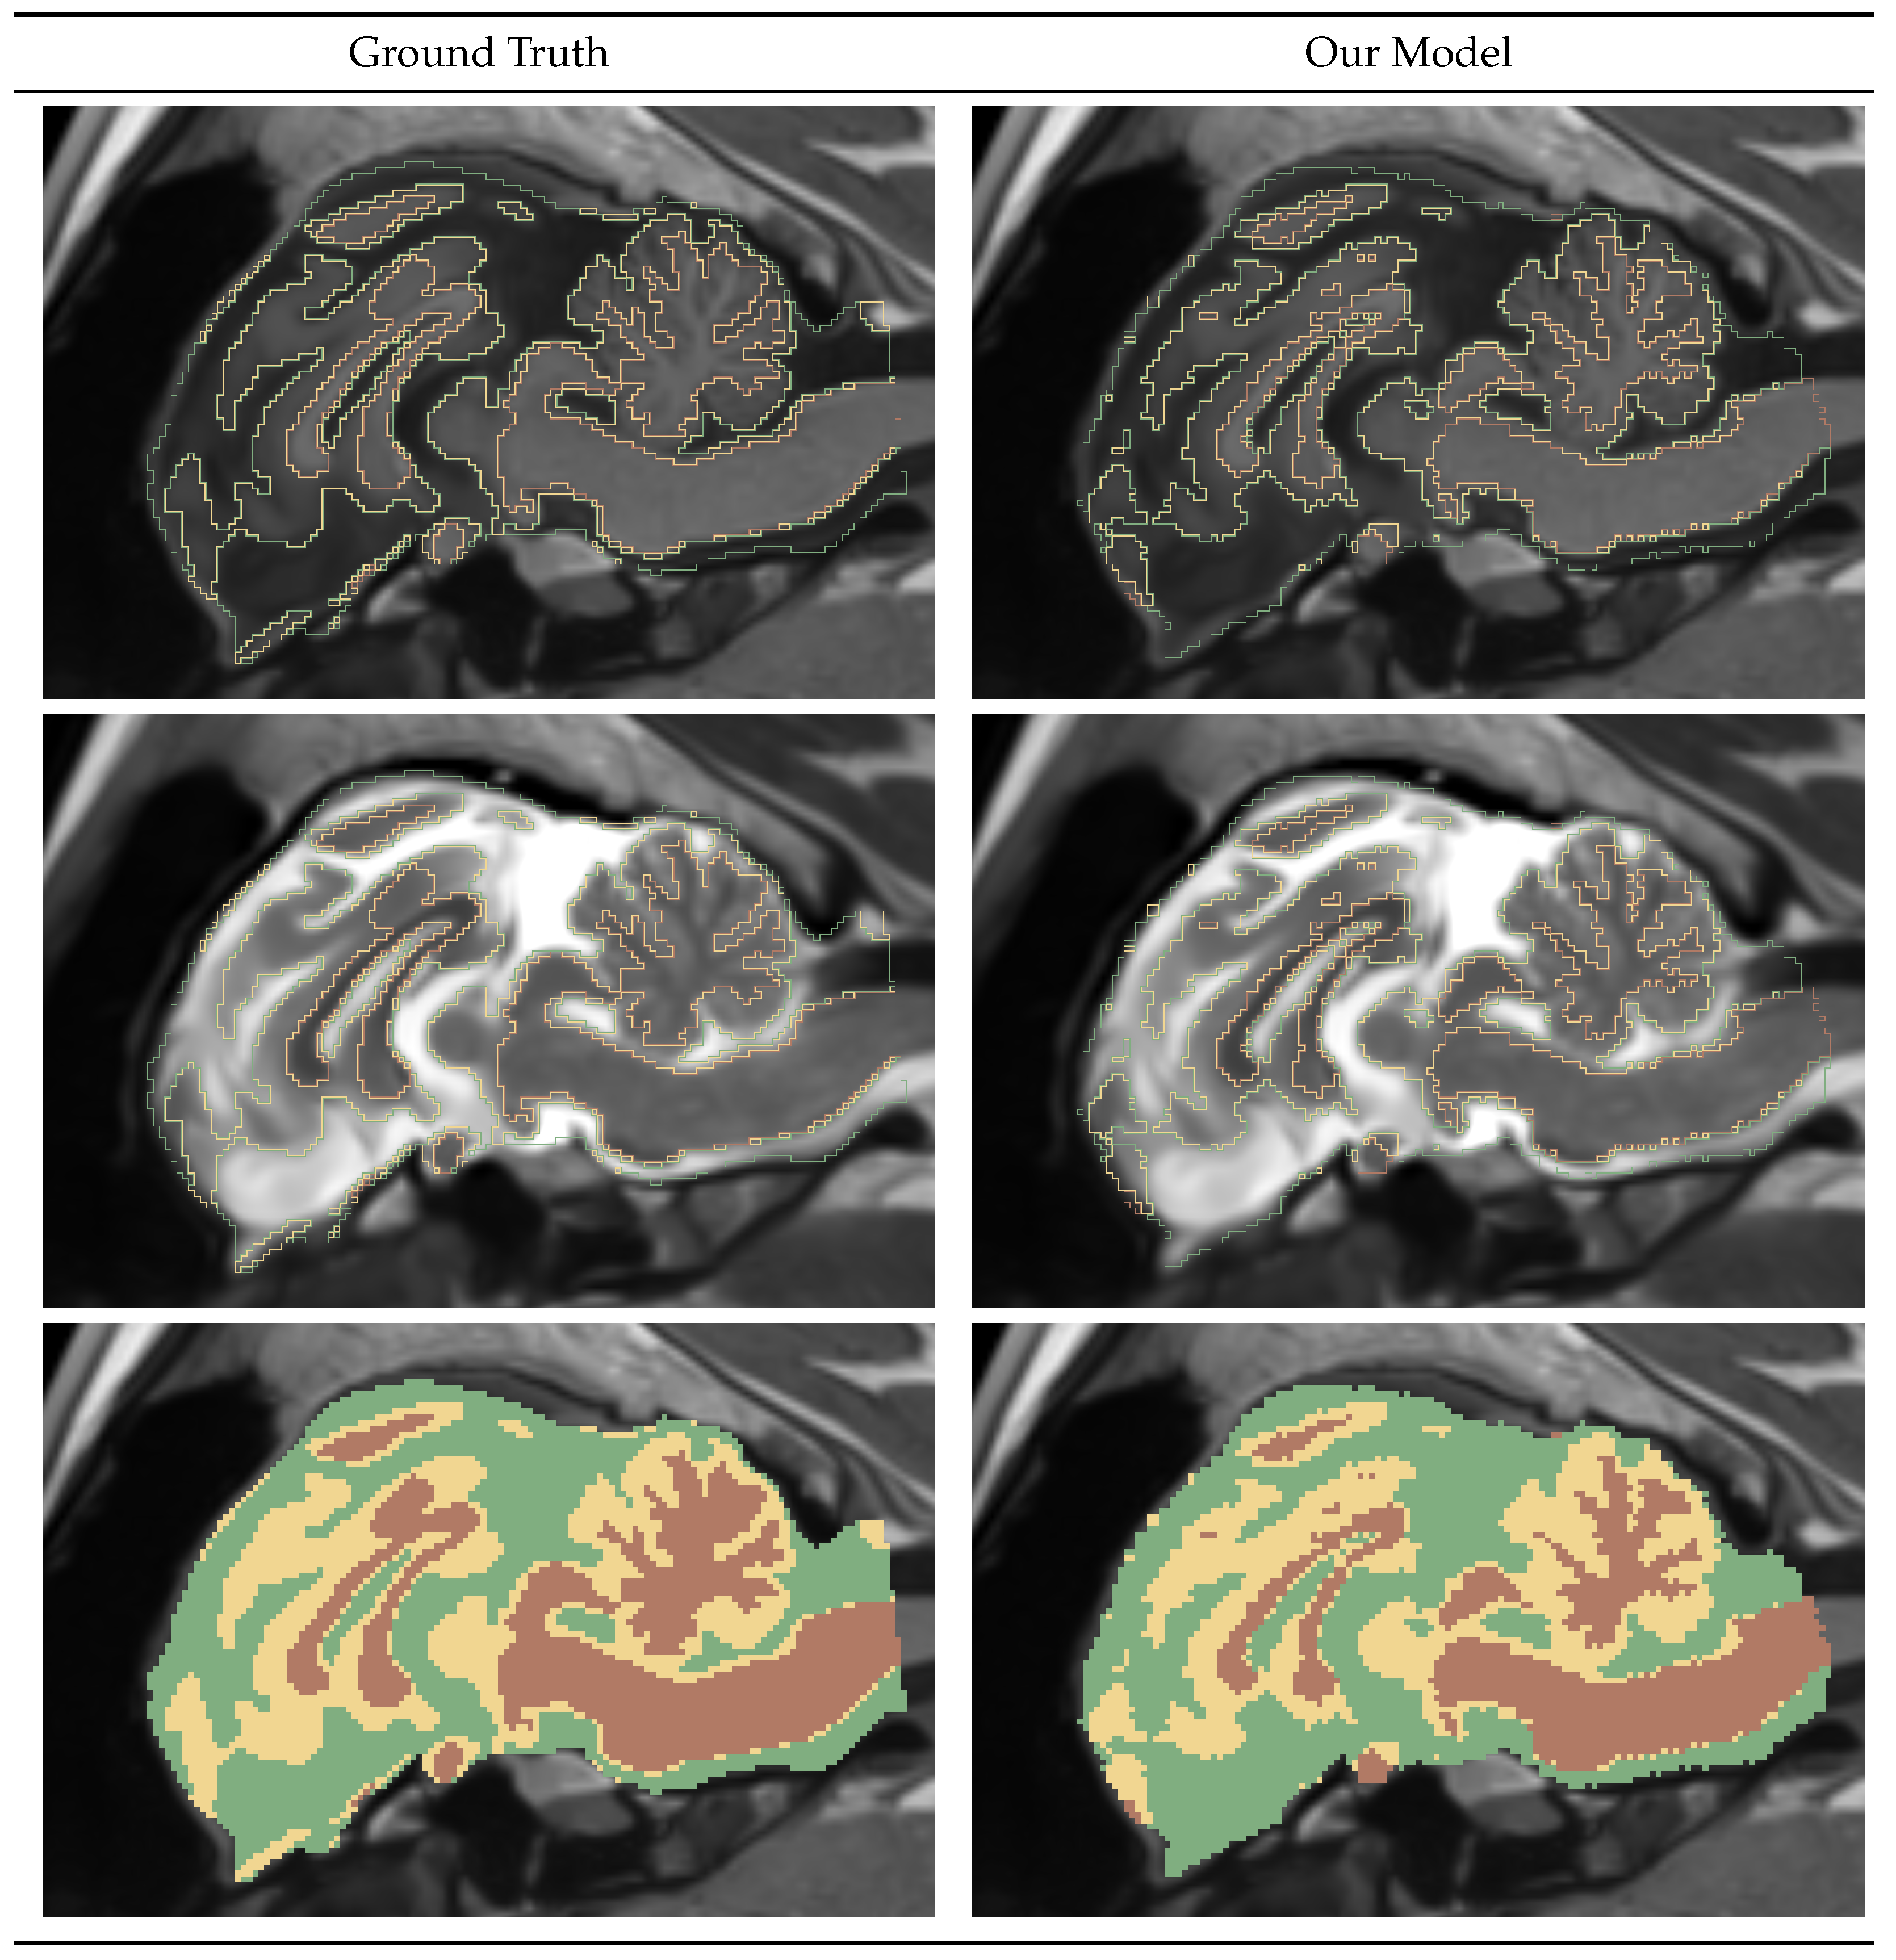

4.1.1. Brainmask

4.1.2. Intracranial Volume Mask

4.1.4. Gray-White-CSF Segmentation Mask

4.2. Pipeline Performance